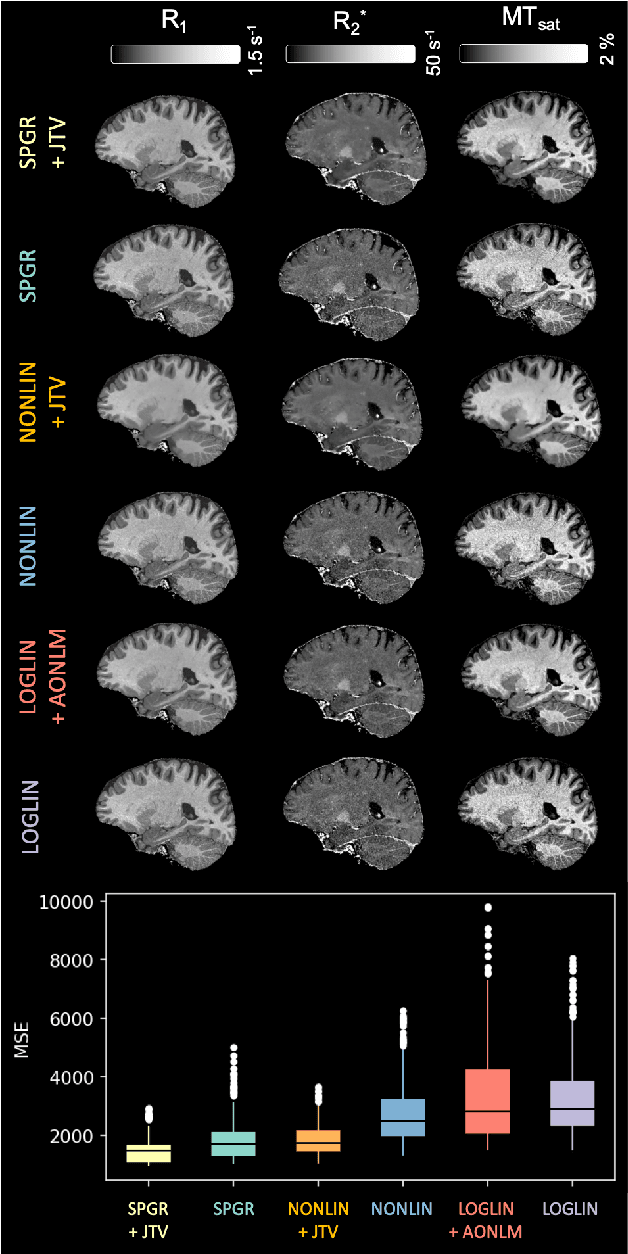

Quantitative MR imaging is increasingly favoured for its richer information content and standardised measures. However, extracting quantitative parameters such as the longitudinal relaxation rate (R1), apparent transverse relaxation rate (R2*), or magnetisation-transfer saturation (MTsat) involves inverting a highly non-linear function. Estimations often assume noise-free measurements and use subsets of the data to solve for different quantities in isolation, with error propagating through each computation. Instead, a probabilistic generative model of the entire dataset can be formulated and inverted to jointly recover parameter estimates with a well-defined probabilistic meaning (e.g., maximum likelihood or maximum a posteriori). In practice, iterative methods must be used but convergence is difficult due to the non-convexity of the log-likelihood; yet, we show that it can be achieved thanks to a novel approximate Hessian and, with it, reliable parameter estimates obtained. Here, we demonstrate the utility of this flexible framework in the context of the popular multi-parameter mapping framework and further show how to incorporate a denoising prior and predict posterior uncertainty. Our implementation uses a PyTorch backend and benefits from GPU acceleration. It is available at https://github.com/balbasty/nitorch.